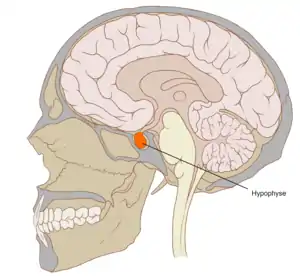

Location of the pituitary gland in the human brain

In vertebrate anatomy, the pituitary gland, or hypophysis, is an endocrine gland, about the size of a pea and weighing 0.5 grams (0.018 oz) in humans. It is a protrusion off the bottom of the hypothalamus at the base of the brain. The hypophysis rests upon the hypophysial fossa of the sphenoid bone in the center of the middle cranial fossa and is surrounded by a small bony cavity (sella turcica) covered by a dural fold (diaphragma sellae).[2] The anterior pituitary (or adenohypophysis) is a lobe of the gland that regulates several physiological processes (including stress, growth, reproduction, and lactation). The intermediate lobe synthesizes and secretes melanocyte-stimulating hormone. The posterior pituitary (or neurohypophysis) is a lobe of the gland that is functionally connected to the hypothalamus by the median eminence via a small tube called the pituitary stalk (also called the infundibular stalk or the infundibulum).

The pituitary gland, in humans, is a pea-sized gland that sits in a protective bony enclosure called the sella turcica. It is composed of two lobes: anterior and posterior, with the intermediate lobe that joins the two regions.[3] In many animals, these three lobes are distinct. The intermediate is avascular and almost absent in human beings. The intermediate lobe is present in many animal species, in particular in rodents, mice and rats, that have been used extensively to study pituitary development and function.[4] In all animals, the fleshy, glandular anterior pituitary is distinct from the neural composition of the posterior pituitary, which is an extension of the hypothalamus.[4]